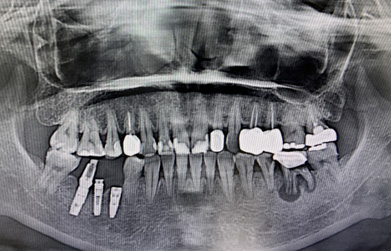

一口潔白整齊的牙齒,可以增加你的自信,讓你盡情展露笑容。但是很多人因為各種原因,從而缺失了自己的牙齒。嚴(yán)重影響的形象美觀及正常咀嚼功能。不過現(xiàn)在種植牙是非常熱門的項目,效果也是很不錯的。 種植